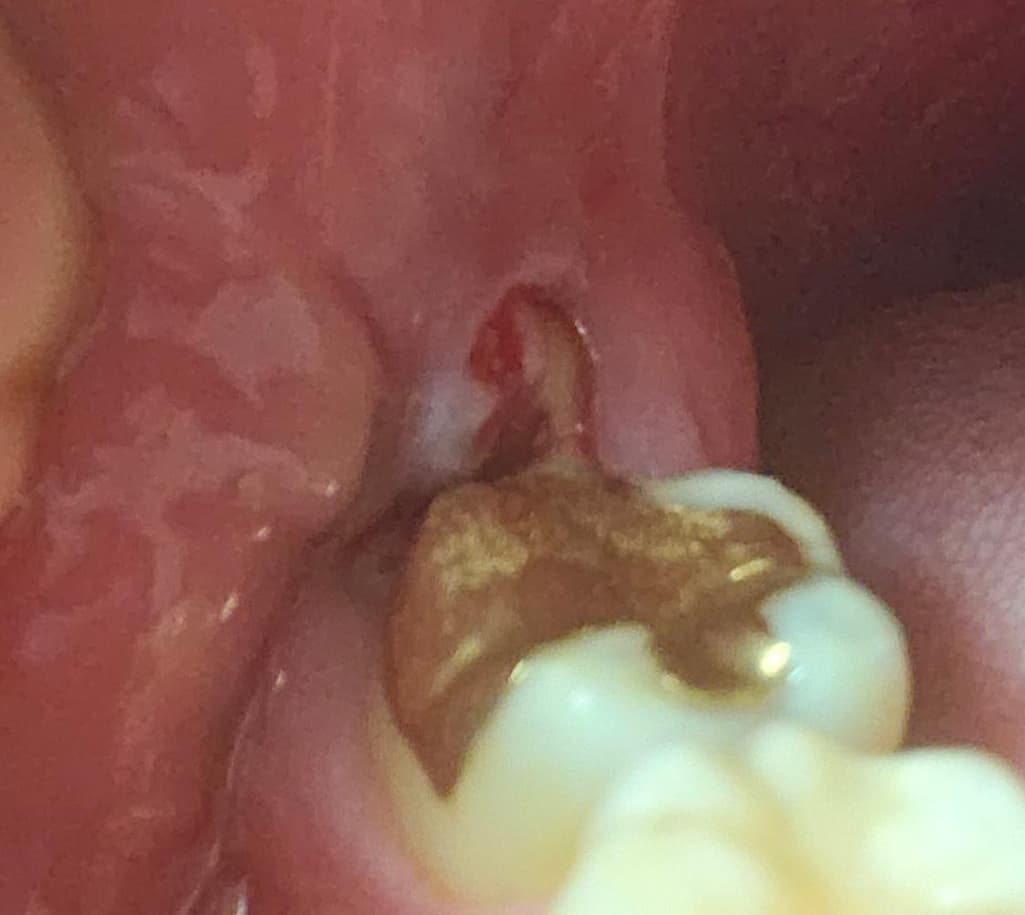

잇몸 염증이 한달사이 재발했는데 어떤 치료해야 할까요?

매복 사랑니 쪽에 염증이 한달 사이에 또 재발했는데 아무래도 재발,충치 방지위해 발치 해야겠죠?

잇몸이 저렇게 부어있어도 발치가 가능한지,

사랑니로 인한 치관주위염입니다 사랑니 발치 안하면 재발가능성이 있습니다 온찜질, 항생제 복용으로 붓기 좀 가라앉히고 그 다음 발치합니다